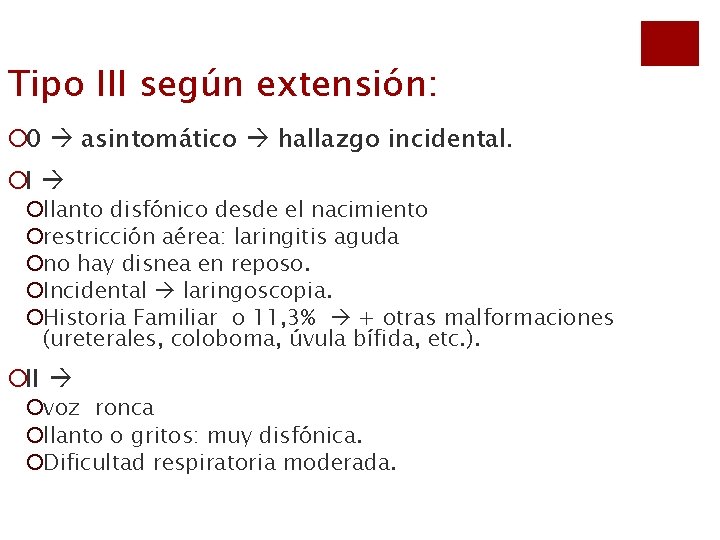

Tipo III según extensión: ¡ 0 asintomático hallazgo incidental. ¡I ¡llanto disfónico desde el nacimiento ¡restricción aérea: laringitis aguda ¡no hay disnea en reposo. ¡Incidental laringoscopia. ¡Historia Familiar o 11, 3% + otras malformaciones (ureterales, coloboma, úvula bífida, etc. ). ¡II ¡voz ronca ¡llanto o gritos: muy disfónica. ¡Dificultad respiratoria moderada.